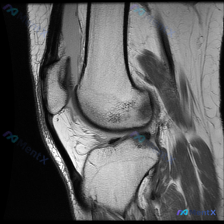

刚整理了一个很有临床意义的病例,核心矛盾是「临床怀疑软骨异常,但现有影像完全正常」,把整个分析思路分享给大家。 病例基础信息 这是一份单张膝关节矢状位T1加权MRI影像,临床提出的核心观察方向是「软骨异常」,无其他临床病史、症状或其他检查资料。 影像具体观察结果 我们先把影像所见说清楚: 1. 骨骼...

看到这个病例挺有代表性的,整理出来和大家分享一下思路。 病例基础信息 这是一张膝关节矢状位T1加权序列MRI影像,用户提出问题:观察图像是否存在软骨异常。 先给大家整理影像评估的基本结果: 1. 骨骼结构:股骨远端、胫骨近端、髌骨皮质连续,骨髓信号未见异常高低信号,关节面形态基本正常 2. 半月板:...

最近遇到一个挺有启发的读片问题,整理出来和大家分享一下: 病例基本情况 这是一份膝关节矢状位T1加权序列MRI,有人提出这份影像可以观察到「软骨异常」,我们先来看详细的影像分析结果: 影像结构整体评估 1. 骨骼结构:股骨远端、胫骨近端、髌骨骨皮质连续,无骨折;骨髓信号正常,无异常低信号提示水肿或占...